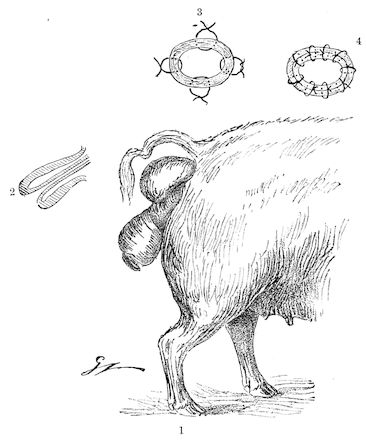

Fig. 3.—Pig suffering from osseous cachexia (fourth stage).

114. The fourth phase, or period of osteomalacia, i.e. softening of the bones, is also the last. It is rarely seen in large animals like horses and oxen, because accidents so often accompany the preceding stages and necessitate slaughter; but it is common in goats and pigs.

In this phase the bones become elastic, soft and depressible, yielding to the pressure of the operator’s fingers.

Fig. 4.—Deformity of the face in the horse shown in Fig. 2.

The flat bones are particularly liable to this change, which is common to domesticated animals. The bones of the head are the first to suffer; later those of the pelvis. The lower jaw becomes swollen, particularly about the centre of the branches which may attain three, four, or five times, their normal thickness.

The depression in the submaxillary space disappears. The upper jaw undergoes similar changes, becoming deformed and thickened until the cavities of the sinuses and the hollow appearance of the palate are lost, while the face is so changed that it cannot be recognised as that of a horse, goat, etc.

The molar teeth are almost buried, their tables alone being visible at the bottom of a depression, the edges of which rise above the neighbouring parts (pig).

Mastication is clearly impossible, the jaws appear paralysed, the muscles powerless, and only swallowing is possible, a fact which explains why life is only prolonged to this stage in animals which can be fed with a spoon or bottle (pigs and goats). The bones of the cranium, although greatly changed in texture, are always less deformed than those of the face.

The changes are such that it is often easy with a mere post-mortem knife to cut the head completely in two. Osseous tissue, properly so-called, has disappeared.

All the constituent tissues, with the exception of the skin and muscles, i.e., the bone, periosteum and aponeuroses, have the appearance and consistence on section of the fibro-lardaceous tissue seen in chronic inflammation.

In the goat, the disease shows some slight peculiarities. Thus, in the second phase, during which goats and sheep suffer so markedly from lameness and pain in the bones, goats often walk on the knees. The disease, however, is uncommon in these animals. The phase of osteoclastia is also less marked and fractures are rare, because the animals weigh less and also because they are less exposed to falls and violent shocks. The bones, nevertheless, are extremely fragile and fractures may be produced at will.

Osteomalacia, on the other hand, is always well marked.

Regarding the development of the disease in pigs, we may repeat what has just been said respecting the goat. Walking on the knees is often one of the first signs, fractures are somewhat rare, and the period of softening and deformity is always very noticeable.